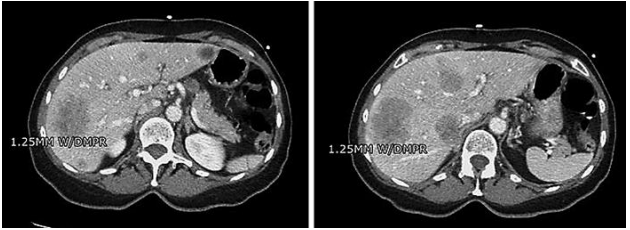

75岁女性,既往有胃食管反流病病史,多次上消化道镜检查和结肠镜检查后出现Barrett食管状态,表现为进行性虚弱、疲劳、食欲减退和弥漫性腹痛,持续3周。患者表示,她正在积极接受针灸治疗,在过去3-5年中,针灸治疗缓解了她的胃食管反流病症状,直到入院前1个月症状恢复。她否认有胃肠道恶性肿瘤家族史。患者承认偶尔有固体食物吞咽困难,最近一个月体重减轻了约5磅,进行性全身无力和跌倒。入院时,除心率为123次/分的心动过速外,生命体征均无异常。体检时,患者反应灵敏,腹部柔软,伴有轻微的上腹部压痛。考虑到患者的心动过速,进行肺部CT血管造影以排除肺栓塞。偶然发现了胃壁增厚,腹腔淋巴结肿大和多个肝脏肿块(图1)。

图1. 有/无静脉或口服造影剂的腹部和骨盆的CT检查显示肝转移灶